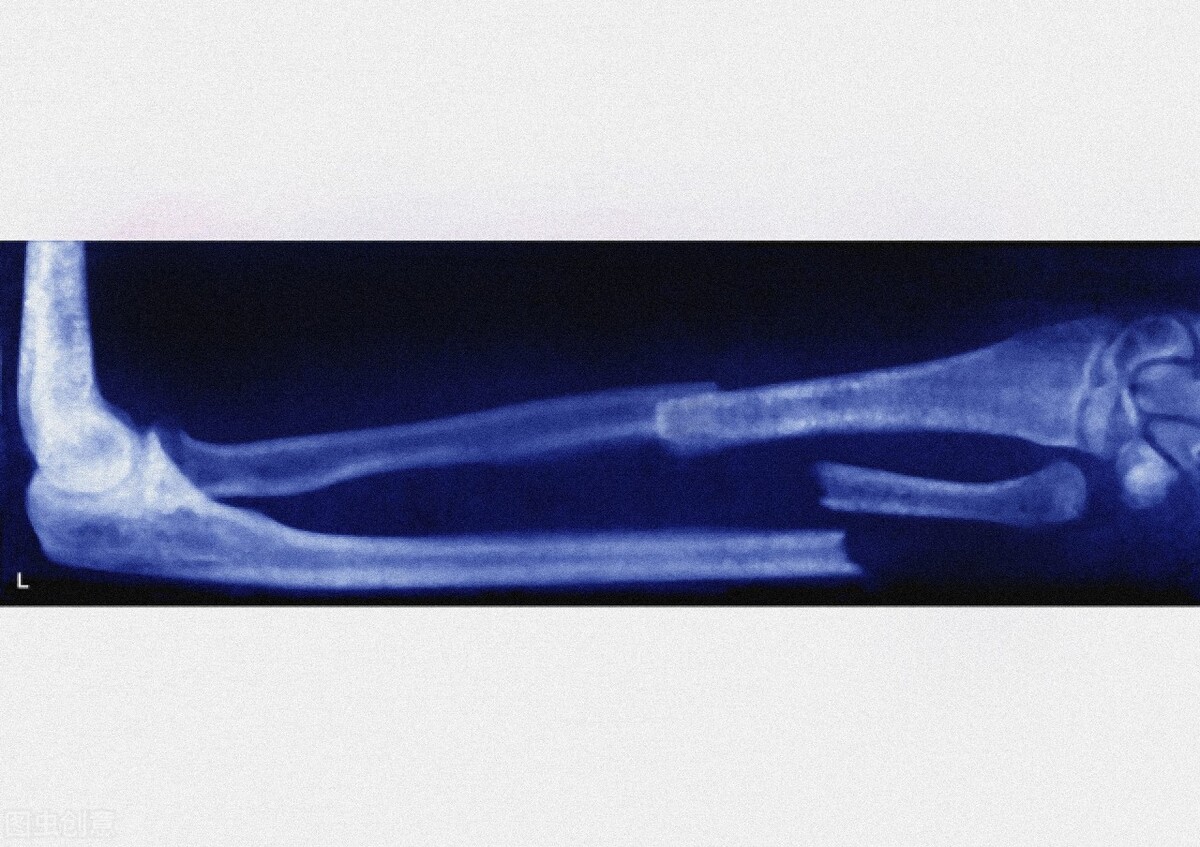

医生继续解释说:这叫病理性骨折,是由疾病引起的。其他的,如摔倒、磕碰,只是一个导火索而已。他这个病,是由于骨质被肿瘤破坏,本身就不结实导致的。

【知识点】病理性骨折是指骨的正常结构与强度,被侵袭性疾病或破坏性病变损害时,在轻微外力或无外力的情况下即可发生的骨折。

导致病理性骨折的病因很多,常见的有以下:转移性骨肿瘤,对骨质造成破坏而引起病理性骨折;感染性骨病,如骨髓炎等,骨髓炎日久对骨质造成了破坏,容易发生病理性骨折;另外,还有良性的骨肿瘤,如骨囊肿等畸形性骨炎;还有代谢性骨病,比如骨质疏松,容易发生病理性骨折。